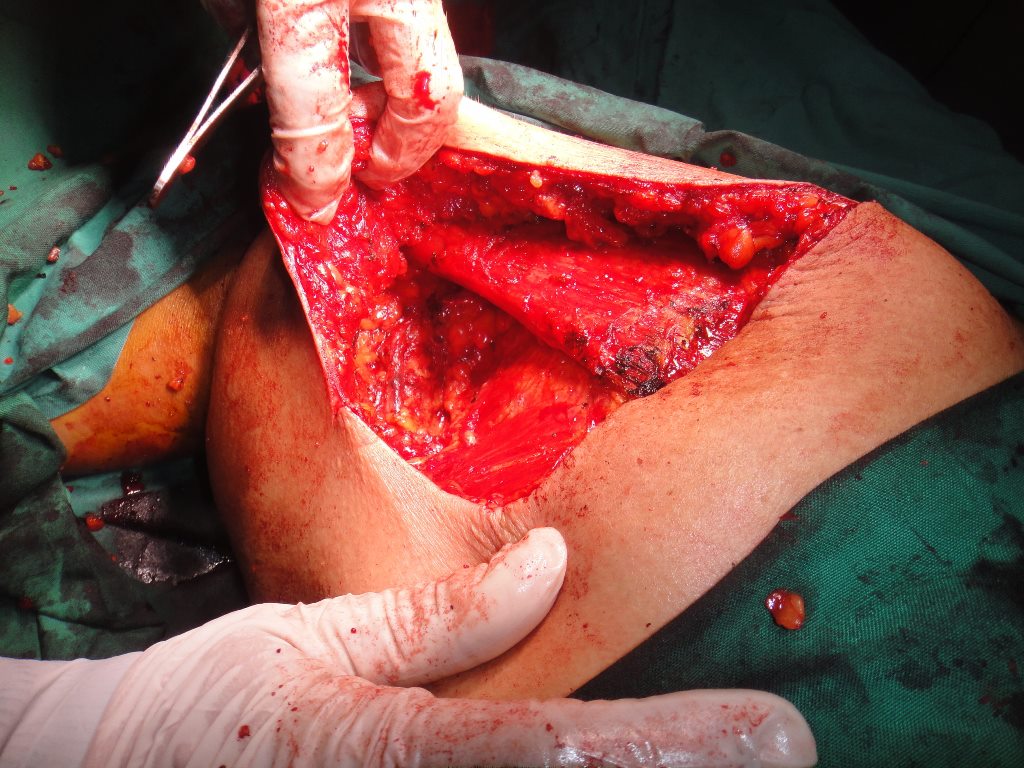

32 YEARS OLD MALE SUFFERING FROM RIGHT LOWER GINGIVO BUCCAL MUCOSA CARCINOMA INVOLVING RIGHT RETROMOLAR TRIGONE.PATIENT HAS ACTIVE PULMONARY TUBERCULOSIS.RIGHT RADICAL NECK DISSECTION WITH RIGHT DISTAL MANDIBULECTOMY WITH RIGHT LOWER ALVEOLECTOMY WITH RIGHT PECTORALIS MAJOR MYOCUTANEOUS FLAPE DONE.